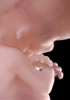

Carnegie Stage 23 (56 post-ovulatory days)

Most embryos at stage 23 are approximately 56-57 postovulatory days old and measure 23-32 mm in length. Distinguishing criteria for this stage include fusion of the eyelids at the medial and lateral margins, clear distinction of the subdivisions of the upper and lower limbs, the forearms appear at or above the level of the shoulders, the superficial vascular plexus of the head is very close to the vertex, and the external genitalia are well developed but not always sufficiently to distinguish the embryo's sex.

(NOTE: These specimens are late stage 23.)